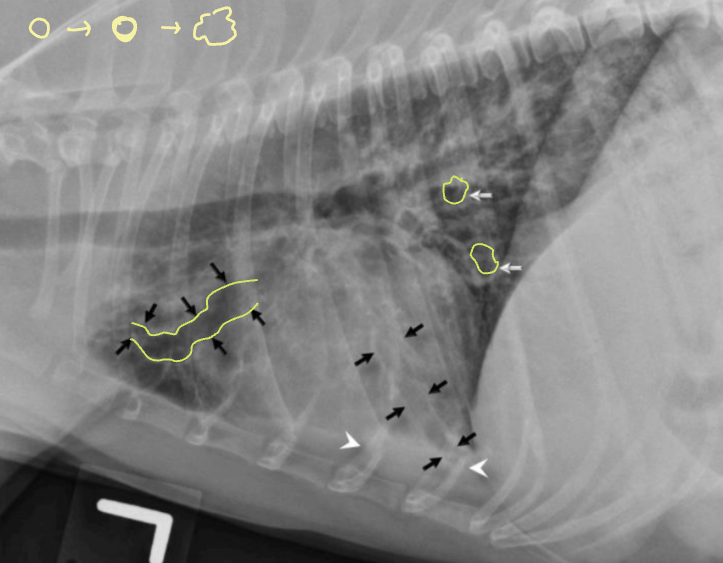

| โณ๏ธ Bronchial pattern (๊ธฐ๊ด์ง ํจํด) | |

| ์ผ์ฆ ์ธํฌ ์นจ์ค์ผ๋ก ๊ธฐ๊ด์ง๋ฒฝ ๋๊บผ์์ง - Doughnut sign : end-on - Tramline sing : side-on ์์ธ - Bronchitis (๋ง์ฑ) - Allergic (Feline asthma, ์๋ฌ์ง์ฑ ํ๋ ด) - Immune-mediated (PIE) ์ฃผ์ - ๋ณด์ธ๋ค๊ณ ํด์ ๋ฌด์กฐ๊ฑด ์ง๋ณ์ X - ๋ง๋จ์์ ๋ค์ ๊ด์ฐฐ๋๋ฉด ์ง๋ณ ๊ฐ๋ฅ์ฑ โ | ![]() ![]() |

| ๊ด๋ จ ์ง๋ณ 1) CCB (Canine Chronic Bronchitis) - ๋ง์ฑ์ ์ธ dry cough - ๋ด๊ฐ์ด ์ข์์ ธ ํธํก ๊ณค๋ | |

| ๊ด๋ จ ์ง๋ณ 2) Bronchiectasis - ๊ธฐ๊ด์ง๊ฐ ํ์ฅ๋๋ค๊ฐ ํ๋ ฅ์ ์๊ณ ํ๋ฌผํด์ง - ๋ง์ฑ์ ์ด๋ฉฐ, ์๊ตฌ์ . ์น๋ฃ ๋ถ๊ฐ. - ํ๋ ด ๋ฐ์ํ๊ธฐ ์ฌ์, ์น๋ช ์ . | ![]() |

| โณ๏ธ Interstitial pattern |

๋ฒฝ์ด ๋๊บผ์์ง๊ณ ๊ณต๊ธฐ๊ฐ ์ฐจ๋ฉด์ ์ง์ ๋ถํ๊ฒ ๋ํ๋๋ ๋ชจ์.![]() |

| + Nodular (๊ตฌ์กฐ์ฑ ๊ฐ์ง ํจํด) : ํ๊ฒฐ์ |

![]() ![]() |

| โณ๏ธ Vascular pattern |

| ํ๊ด์ด ์ปค์ ธ์ ํ๊ฐ ์ง์ ๋ถํด ๋ณด์ด๋ ๋ชจ์ |

| 1) Pulmonary hypertention - HW infection (์ฌ์ฅ์ฌ์์ถฉ) |

![]() |